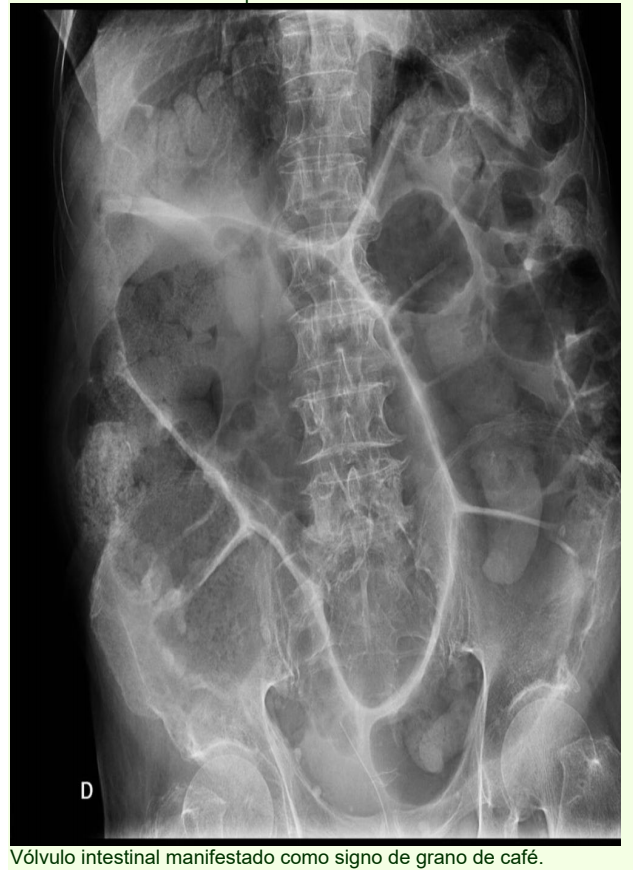

• Signo del grano de café: Cuando la causa es un vólvulo del sigmoides

Es útil para detectar obstrucción del intestino delgado, sobre todo si la obstrucción es consecuencia de una causa extrínseca, como pueden ser tumores o abscesos; también son útiles para detectar sitios de estenosis con dilatación proximal y asas vacías distales.  Los vólvulos del tracto gastrointestinal constituyen una causa importante de abdomen agudo. El examen de elección es la tomografía computada, ya que permite observar el vólvulo, así como posibles diagnósticos diferenciales.  Tiene una alta sensibilidad para confirmar el diagnóstico, localizar el sitio de obstrucción e identificar la causa en la gran mayoría de los casos así como evaluar la presencia de complicaciones al permitir evaluar la vasculatura, los omentos, los mesenterios, el peritoneo, etc; en algunos casos es necesario administrar a través de la sonda nasogástrica material de contraste, por lo general hidrosoluble como el gastrografin; si se instila bario y existe perforación del intestino se corre el riesgo de salida del mismo, con la consecuente adherencia firme al peritoneo; en general, la TAC tiene sensibilidad de 80 a 90% y especificidad de 70 a 90%